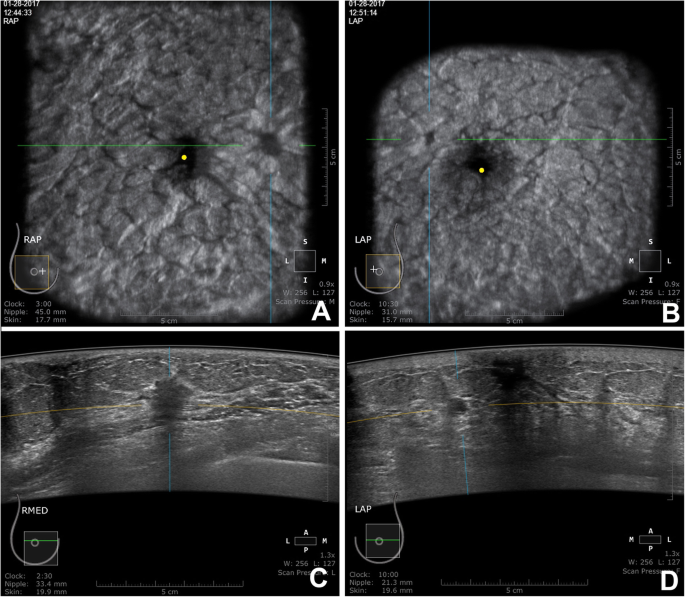

Ultrasound (USG) Both Breast Scan is a specialized imaging examination used to evaluate both breasts for any abnormalities or changes in breast tissue. This non-invasive procedure employs high-frequency sound waves to create detailed images of the breast tissue, including the mammary glands, ducts, and surrounding structures. By examining both breasts simultaneously, radiologists can compare any differences in breast tissue and identify any suspicious findings such as masses, cysts, or areas of increased vascularity. USG Both Breast Scan is commonly used as a supplementary imaging tool alongside mammography or as a primary screening method for women with dense breast tissue or those at higher risk for breast cancer. It plays a crucial role in early detection, diagnosis, and monitoring of breast conditions, ultimately contributing to better outcomes and management of breast health.

Ultrasound (USG) Single Breast Scan is a focused imaging procedure used to examine a specific breast for any abnormalities or changes in breast tissue. This non-invasive technique utilizes high-frequency sound waves to produce detailed images of the breast, including the mammary glands, ducts, and surrounding structures. By concentrating solely on one breast, radiologists can closely evaluate any identified masses, cysts, or areas of concern, aiding in the diagnosis and management of breast conditions such as tumors, cysts, or fibroadenomas. USG Single Breast Scan is often recommended when a specific area of interest is identified during a clinical breast examination or mammography, providing additional information to guide further evaluation or treatment decisions.